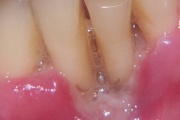

Krooniline parodontiit

ANUG (äge nekrotiseeruv haavandiline gingiviit/parodontiit)

Parodontiit